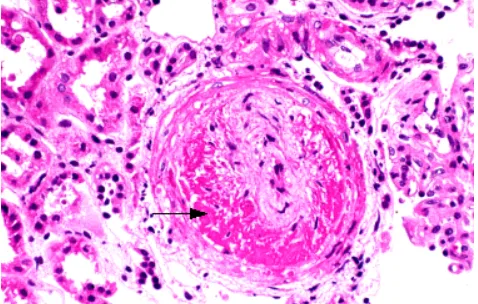

(1)内皮改变和微血栓:

小血管改变:较小微动脉和毛细血管

内皮细胞和内皮下间隙水肿,血管壁增厚和血小板微血栓

使血管腔消失(尤其是较小血管),并可导致血管发生透明闭塞。

肾脏的病理改变包括微动脉和肾小球血栓。